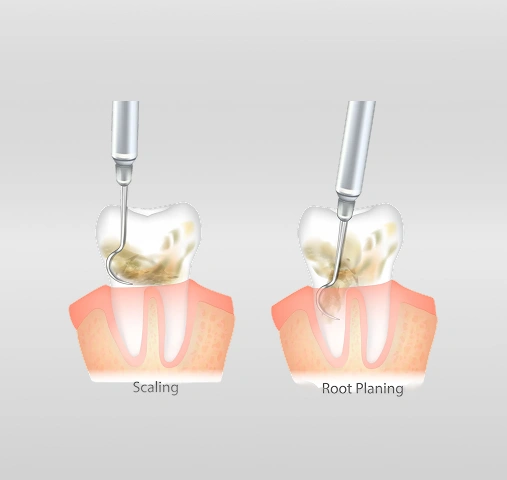

Scaling

Plaque and tartar (hardened plaque) are carefully removed from the surfaces of your teeth, including areas below the gum line.

Root Planing

The roots of your teeth are gently smoothed to remove bacteria and toxins, making it harder for plaque to reattach.